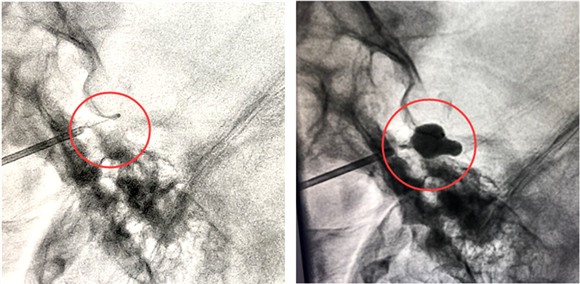

秉承“精益求精,开拓创新”,尽最大努力为患者解除病痛的理念,陈维福教授通过不断学习国内外先进技术,成功引进三叉神经半月节微球囊压迫术。该手术系微创手术,具有创伤小,手术时间较短,几例手术均在半小时内完成;清醒后疼痛即刻缓解,疗效确切;术后恢复时间短,术后3天便可出院;价格低廉等优点。适用于:1.体质较弱、年龄较大不能耐受开颅微血管减压手术患者。2.射频消融手术或开颅术后复发的患者。3.保守治疗无效的患者。